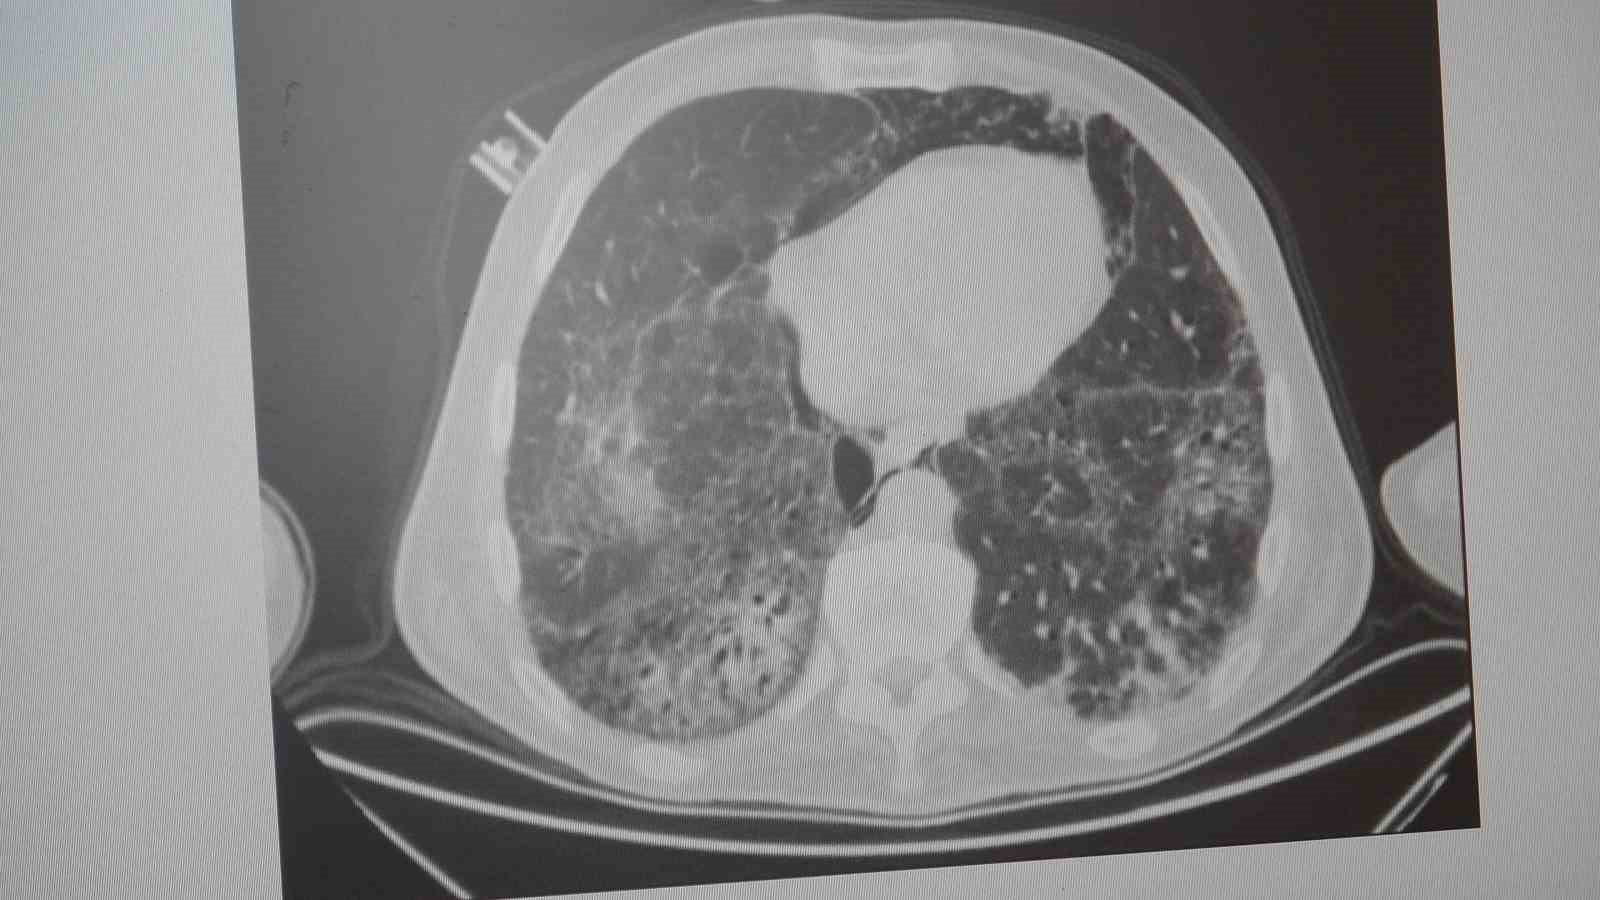

"KOAH toplumda sık görülen bir hastalıktır ve yaklaşık toplumda bunu yüzde 10 civarında görüyoruz. KOAH, zararlı maddelerin akciğeri parçalamasıyla oluşan bir rahatsızlık ve bunun da en önemli nedeni sigara. Vakaların aşağı yukarı yüzde 85’i sigara kullanımından kaynaklıdır. Bunun dışında hava kirliliği, iş yerlerinde kimyasal maddelere maruz kalma ve enfeksiyonlar da yine KOAH’ın nedenleri arasındadır. KOAH’ın önemi şu; bugün Dünya Sağlık Örgütü’nün (DSÖ) dünyada insanları öldüren hastalıklar listesinde ilk 10’da 4’üncü sırada yer alıyor. KOAH önlenebilir bir rahatsızlıktır; sigaranın bırakılmasıyla birlikte tamamen ortadan kalkacaktır."

KOAH’ın akciğer dokusunu tahrip eden bir hastalık olduğunu ve bu nedenle de hastaların enfeksiyona açık hale geldiğine dikkat çeken Karakurt, "Akciğer dokusunun tahrip olduğu her durumda hastaların enfeksiyona karşı eğilimi artar ve enfeksiyona yakalandıkları zaman bunun geçmesi güç olur. KOAH’lı hastalar zatürre geçirdikleri zaman öksürük ve balgam artışı gibi bir takım belirtiler gelişir. Ayrıca ateşin 38,5 derecenin üstüne çıkması, nefes darlığının artması, titremeyle birlikte ateşin yükselmesi ve bir takım bilinç bozukluğu gibi belirtiler hastanın zatürre olduğunu gösterebilir. Bu nedenle hastaların erkenden doktora başvurmaları önemlidir" şeklinde konuştu.